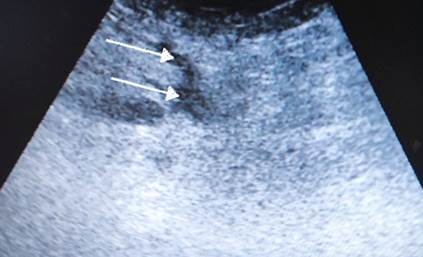

Выполнена операция TAR с имплантацией стандартной полипропиленовой сетки 30х40 см. Этапы вмешательства соответствовали общепринятым для этого хирургического пособия [5]. Проведена профилактика инфекций области хирургического вмешательства (ципрофлоксацин 400 мг внутривенно перед вмешательством и далее 2 раза в сутки) и венозных тромбоэмболических осложнений (эноксапарин 0,4 мл подкожно 1 раз в сутки). Активизирован в 1-е сутки после операции. На 5-й день отмечена лихорадка до 39 ºC. Тест на COVID-19 отрицательный, на фронтальной рентгенограмме легких инфильтративных изменений нет. На ультразвуковом исследовании (УЗИ) выявлены жидкостные скопления в ретромускулярном пространстве и в ране (рис. 3). При пункции получен серозно- геморрагический экссудат, проводилась антибиотикотерапия (имипенем/циластатин 500 мг 3 раза в день) без эффекта, высокая температура сохранялась. Появились гиперемия брюшной стенки (рис. 4) и повышение уровня C-реактивного белка до 245 мг/л. Заподозрена флегмона передней брюшной стенки, выполнена ревизия раны, получен серозно-геморрагический экссудат без примеси гноя. Установлена система терапии отрицательным давлением -130 мм рт. ст. (в англоязычной литературе – NPWT, negative pressure wound therapy, рис. 5). Клинического эффекта не было, сохранялись интоксикация и высокая температура.

Рис. 3. УЗИ брюшной стенки первого пациента после операции. Белыми стрелками показаны жидкостные скопления